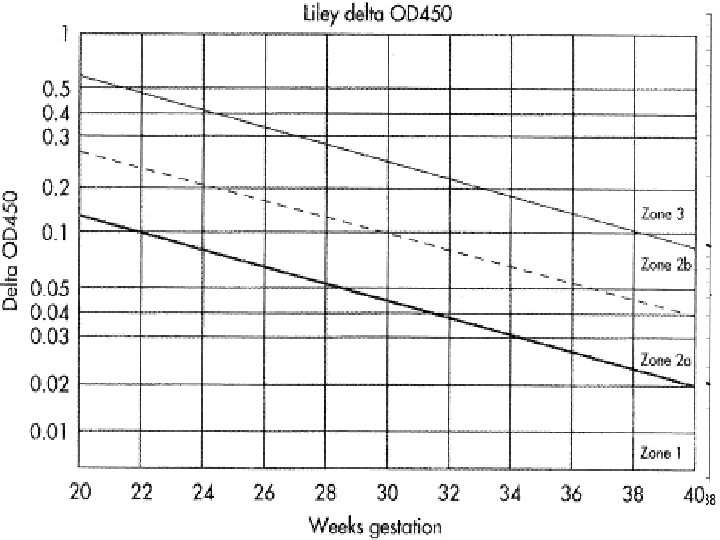

Liley chart Originated by liley in 1961, he compared ∆OD 450 measurements with fetal outcome in 101 isoimmunized pregnancies and showed that Mild, Moderate, or Sever fetal anemia could be predicted according to which of three zones the bilirubin level was plotted into ∆OD 450 = optical density deviation.

Queenan curve (Deviation in amniotic fluid optical density at a wavelength of 450 nm in Rh-immunized pregnancies from 14 to 40 weeks' gestation)

Zone 1 →fetus unaffected (Rh negative) or have only mild disease →repeat sampling in 2 to 3 weeks Zone 2→ if in lower part→ fetus at moderate risk→ HB level between 11 to 13 g/dl whereas in the upper part HB level between 8 to 10. 9 g/dl → repeat sampling within 1 to 2 weeks if in lower part, if in upper part delivery is indicated.

Zone 3→ severely affected fetus with HB level of less than 8 g/dl and without therapy death is predicted within 7 to 10 days immediate fetal red blood cell transfusion or delivery ACCORDING TO GESTATIONAL AGE l